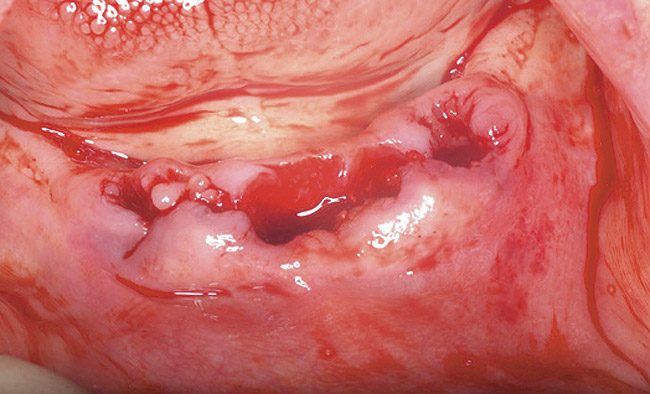

Bisphosphonate-related osteonecrosis of the jaws (BRONJ) is characterized by the presence of exposed bone in the oral cavity for more than 8 weeks in a patient who has been taking bisphosphonates and who has not had any radiation therapy in the oral cavity3 (Figure 1). The risk of BRONJ from the use of oral bisphosphonates is very low, currently about 1%.8 Most researchers believe this incidence is so low because it takes many years for the drug to saturate the bone. Most cases of BRONJ from oral bisphosphonates occur after at least 3 years of drug use.9 However, a recent study by Cartsos et al of over 700,000 medical claims found no increased incidence of inflammatory conditions, including osteonecrosis.10

Figure 1  Exposed bone in the mandibular jaw that is characteristic of BRONJ. Photo courtesy of Robert Marx, DDS.

Figure 1